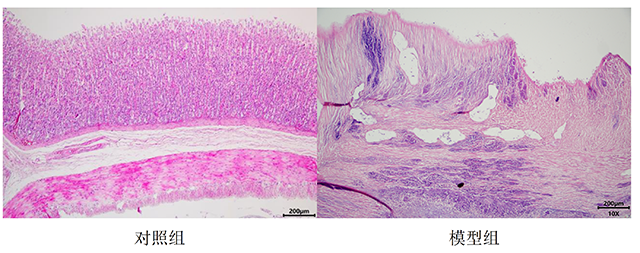

- 造模后变化:一般术后3~5天即可形成胃溃疡。用此法诱发的胃溃疡,醋酸注射后第5天形成典型圆形溃疡(直径4.2±0.8 mm),深达肌层;第12天模型组愈合率仅41%,而楹树提取物组溃疡面积缩小38.4%(P<0.05),TNF-α下降43.8%。一般在60天左右可自行愈合,但也有个别在200天后仍可见较大的溃疡。溃疡的大小、深度与醋酸的浓度和注射剂量密切相关。

醋酸型胃溃疡大鼠胃组织HE 染色切片图

胃组织HE染色

五、模型总结:醋酸慢性胃溃疡模型是勋博生物核心实验服务平台的核心技术之一,其病理进程(坏死-炎症-肉芽增生)与人类溃疡高度一致,已支持46项药物临床前研究,数据可重复性达ISO认证标准(CV<8%)。醋酸诱导慢性胃溃疡模型的构建方式是一种可靠且常用的实验方法,可用于研究胃溃疡的发病机制、药物治疗效果等方面。但需注意实验过程中的细节控制,以确保实验结果的准确性和可靠性。